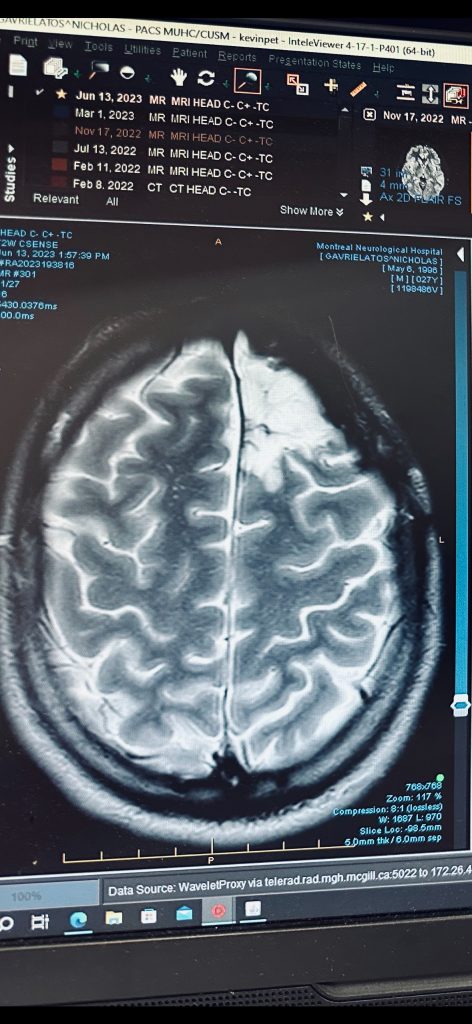

When Gavrielatos was only 15 years old, during an MRI after an injury, doctors discovered a tumour in his left frontal lobe requiring surgery.

The procedure was successful, but 10 years later — the tumor returned, just as Gavrielatos was about to begin writing his master’s thesis. A second surgery was needed and despite months of physical and cognitive challenges, he completed his master’s program at Concordia University’s John Molson School of Business.

Gavrielatos continues to be seen by his neurosurgeon, Dr. Kevin Petrecca.